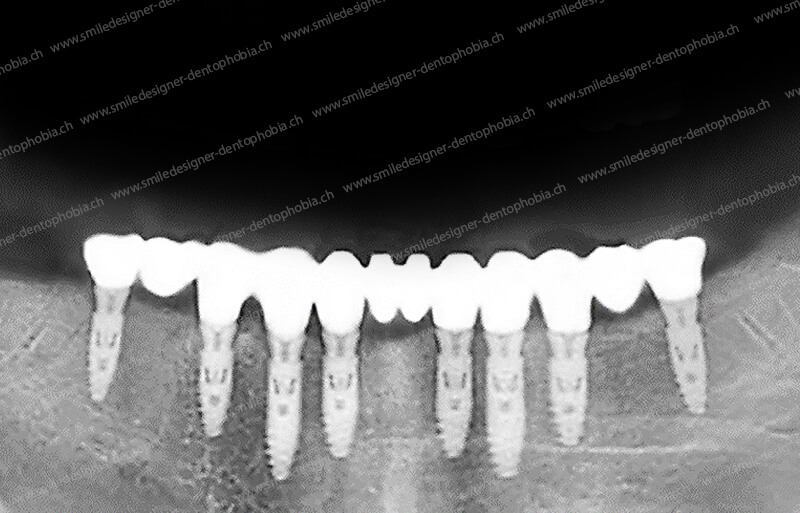

Cas clinique « GOLD STANDARD MCI » mandibulaire : Bridge implanto-porté sans extension postérieure (ALL ON 8). Version définitive du bridge avec un cosmétique en céramique.